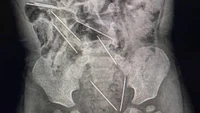

Sebuah hasil rontgen menunjukkan ada sekitar 800 jarum 'susuk' yang bersarang di tubuh seorang wanita. Radiografi perut dari pasien yang sama juga menunjukkan jarum berada paling banyak di area panggul. (Foto: Journal of Radiology Case Reports)

Sebuah hasil rontgen menunjukkan ada sekitar 800 jarum susuk yang bersarang di tubuh seorang wanita. Radiografi perut dari pasien yang sama juga menunjukkan jarum berada paling banyak di area panggul. (Foto: Journal of Radiology Case Reports)